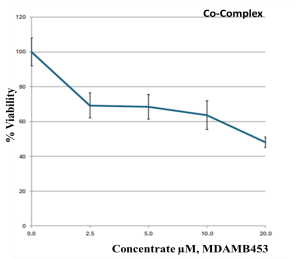

2.9. Cell Proliferation Assessments

| Parameter | Dilution Used to Treat the Cells with the Metal Complexes/µg | ||||

|---|---|---|---|---|---|

| |||||

| Co–ligand complex 1:1 |   | ||||

| Drug conc µg | 0 | 2.5 | 5 | 10 | 20 |

| Mean—blank | 100 | 69.2 | 68.4 | 63.6 | 48.1 |

| Standard deviation | 8.00 | 7.15 | 7.08 | 8.29 | 3.07 |

| HEK293 | - | - | - | - | 80.50 ± 3.139 |